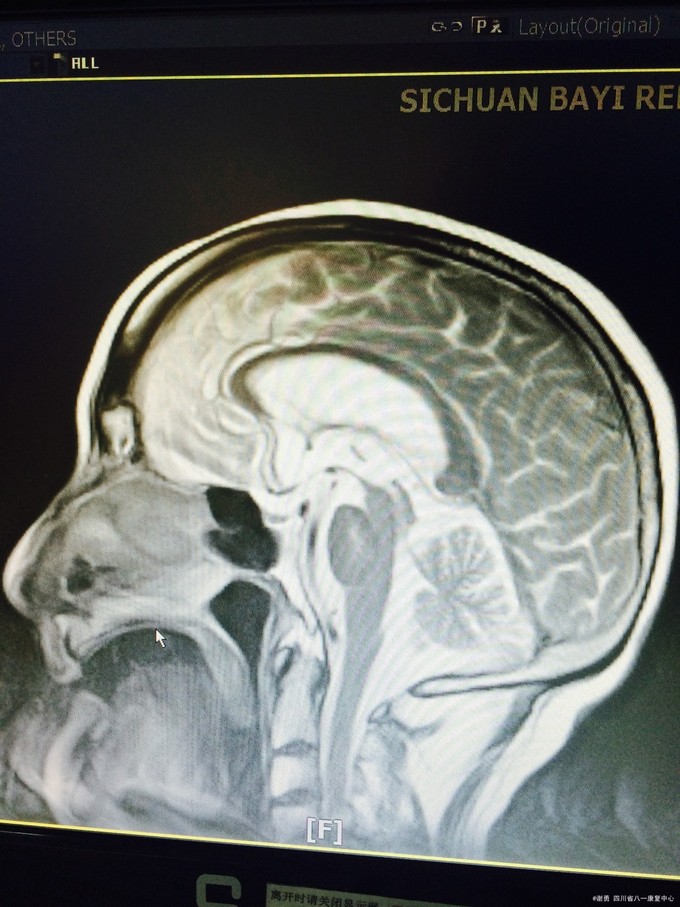

入院查体:血压165/100mmHg,扶入病房,查体合作欠佳,反应迟钝,语言缓慢,记忆力下降,定向力基本正常。四肢肌张力正常。双上肢肌力5级,下肢4级,双下肢病理征阳性;深浅感觉粗测正常。MMSE评分:18分; 辅助检查:血常规,肝肾功、血糖、电解质均正常。头颅MRI 及MRA示:双侧半卵圆中心、脑室旁,基底节区、右侧丘脑、脑干多发缺血灶改变;脑萎缩,脱髓鞘改变;双侧颈内动脉C1-4段边缘欠规则,信号欠均匀。

入院诊断考虑:皮层下动脉硬化性脑病。治疗上主要给以积极改善大脑微循环,控制高血压危险因素,营养神经,改善认知、 记忆功能。治疗半月余,患者症状明显改善,MMSE评分:24分。

出院后口服氨氯地平控制血压,银杏叶、胞二磷胆碱片改善认知,阿司匹林肠溶片卒中二级预防,定期随访!皮层下动脉硬化性脑病又称Binswanger病、进行性皮层下血管性脑病。为老年人在脑动脉硬化基础上,大脑半球白质弥漫性脱髓鞘性脑病。大多发生在50岁以上,在老年人中发病率为1%~5%,男女发病相等。主要累及侧脑室周围、半卵圆中心等皮层下脑深部白质,多为双侧性,常伴有腔隙性脑梗死、脑萎缩。